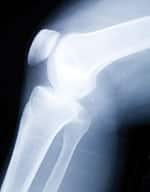

Painful joint deterioration caused by osteoarthritis ranks among the most common, debilitating conditions confronting aging individuals today. It is also rapidly on the rise, in both young and old alike due to excess body weight. An estimated 27 million Americans age 25 or older currently suffer from osteoarthritis.1 By 2030, a projected 67 million people will have doctor-diagnosed arthritis.2 A new therapy might reverse this trend. The technology is called autologous stem cell transplantation. It involves using undifferentiated cells that can develop into almost any tissue—new cartilage, tendons, ligaments, even bone—to replace damaged, arthritic joints. These cells are taken not from human embryos but from your own body! At the forefront of this research is Colorado-based regenerative medical expert Dr. Christopher Centeno. His clinical work has already yielded intriguing preliminary results—up to 75% pain reduction without surgery or side effects in scores of patients. In this article, the facets of Dr. Centeno’s new therapy are detailed. You will then learn of the FDA’s inhumane attempt to block Dr. Centeno from using this experimental therapy. In this instance, the FDA is erecting a regulatory barrier to deny patients access to their own stem cells—in all likelihood to protect drug company profits. Osteoarthritis: The Scourge of Aging IndividualsOsteoarthritis is a progressive condition for which no cure exists. Affected joints undergo gradual degradation of cartilage, the natural slippery, lubricated tissue that allows smooth movement and weight-bearing.3 As the cartilage deteriorates, friction increases, leading to severe pain and ultimate destruction of the joint.4 In one of nature’s seeming cruelties, cartilage is poorly supplied with blood, making it slow to heal. Worse, damaged cartilage will not regenerate itself under normal circumstances.5,6 Since osteoarthritis is common in previously physically active people, it can significantly impair quality of life in those who suffer from it, particularly as they age.7-9

Many modern surgical repair procedures are aimed at disrupting cartilage deeply enough to trigger a natural repair response from the bone underlying the cartilage—but the result is often incomplete and inadequate.9,10 Over the past several decades, surgeons have developed techniques for removing small “plugs” of healthy cartilage from uninvolved areas of joints and transplanting them into the damaged areas, sometimes culturing the cells first to increase their numbers.4,6 While these techniques have shown some promise, they have the disadvantages of damaging otherwise intact cartilage without adequately restoring joint function.5,9 Another challenge osteoarthritis poses for clinicians has to do with aging itself: in the case of knee replacements—one of the most common procedures—the “repair” does not last for a long time, so orthopedists paradoxically delay the first surgery for as long as possible. For this reason, all too many osteoarthritis sufferers are told to wait until the disease becomes severe enough, or they grow old enough, to warrant full-scale artificial knee replacement surgery. Until then, they must rely on pain relievers or periodic injections of anti-inflammatory steroid drugs while they get older in pain. When they finally do have the procedure performed, they face yet another lengthy period of debilitation: total knee replacement is major surgery, with patients typically advised to count on up to 6 weeks of limited activity, and 6-12 months of gradual rehabilitation to return to normal function.11 That alone explains orthopedists’ keen interest in discovering faster and simpler solutions. Personalized Therapy Using Your Own Stem CellsMost people have heard of stem cells—the powerful “precursor” cells that can differentiate, or mature, into virtually every type of tissue in the body. Early work with stem cells involved “harvesting” them from human embryos, which raises a host of ethical issues. Also of concern is the fact that embryonic stem cells, precisely because they are so versatile, carry the risk of transforming into tumor cells.12

Accordingly, scientific attention has focused of late on alternatives to embryonic stem cell therapies. When it comes to bone and joint regeneration, the most promising approach to emerge in recent years is the use of so-called mesenchymal stem cells (MSCs) taken directly from your own body.13 Unlike embryonic stem cells, mesenchymal stem cells have already differentiated to some extent, “committing” themselves to develop into tissues such as bone, muscle, tendon, ligament, and cartilage.13,14 They can be found in abundance in your bone marrow.14 Under the proper conditions, MSCs can be induced to differentiate into each of their potential specific tissue types, making them the ideal “seeds” for implanting into damaged joints and bones. One advantage of using MSCs from your own body (autologous) is there is zero risk of transplant rejection. There is even evidence that transplanted MSC’s exert anti-inflammatory, immune-modulating influences within the joint.4,15 This means they can theoretically outperform more traditional transplants, which run the risk of destruction by inflammation. For years, the burning question among researchers in the field has been: will MSC (mesenchymal stem cell) transplants prove effective in human patients with osteoarthritis? Thanks to the work of Dr. Christopher Centeno, an international expert and specialist in regenerative medicine, the answer may be yes! Dr. Christopher Centeno’s Healing ApproachBased at Regenerative Sciences in Westminster, Colorado, Dr. Centeno first became interested in applying what was known about the powers of stem cells to solving problems in orthopedics roughly a decade ago. Because orthopedics is the practice of medicine devoted to the health of bone, joint, muscle, and connective tissue, mesenchymal stem cells (MSCs) were the obvious choice for his research. Centeno was aware of the rapidly growing success of MSCs in animal studies, and the failure rate of existing therapies for osteoarthritis and similar diseases.16 He knew that human bone marrow contained an adequate supply of MSCs that could readily be “harvested” from a patient’s own hip bone. He theorized the patient’s own tissue growth factors, obtained from a “puree” of their own platelets—the clotting factors contained within the blood—could be used to trigger MSCs to develop functional cartilage and bone to repaired damaged joints.16 Once the cells had been “amplified” in culture with activated platelets, they could be injected into a diseased joint. Animal studies had demonstrated that such cells would proceed to further differentiate into the proper cell types based on local tissue factors produced by the surrounding healthy structures. In two seminal 2008 papers, Centeno presented the results of his first human patient, an individual with a long history of chronic knee pain that proved unresponsive to surgery.13,16 Centeno’s patient underwent successful harvest, expansion (through platelet-derived tissue factors), and transplant of his own MSCs into his damaged knee joint. The results were compelling—just one month after the injection the patient’s cartilage surface had expanded by approximately 20%, a gain that was maintained at three months. And the meniscus (the lower cartilage that actually bears weight) was nearly 29% larger in volume at 3 months, indicating vigorous growth and remodeling of previously damaged tissue. Just as critically, the patient’s pain level dropped from 4 out of 10 to less than 1 out of 10, and his range of motion, previously limited, returned close to normal.